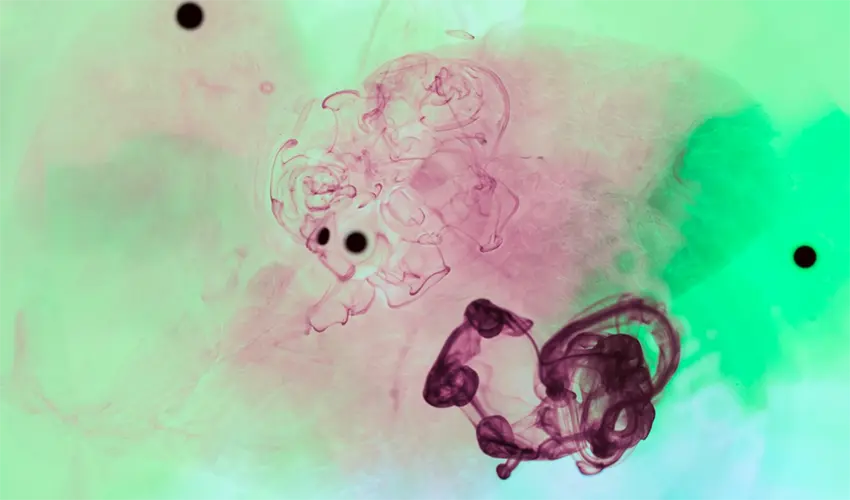

Direct Smear for Fungi (KOH)

• Direct Smear for Fungi (KOH): A sample (skin, nail, or hair) is treated with potassium hydroxide (KOH) to dissolve non-fungal material, allowing direct visualization of fungal elements under a microscope.